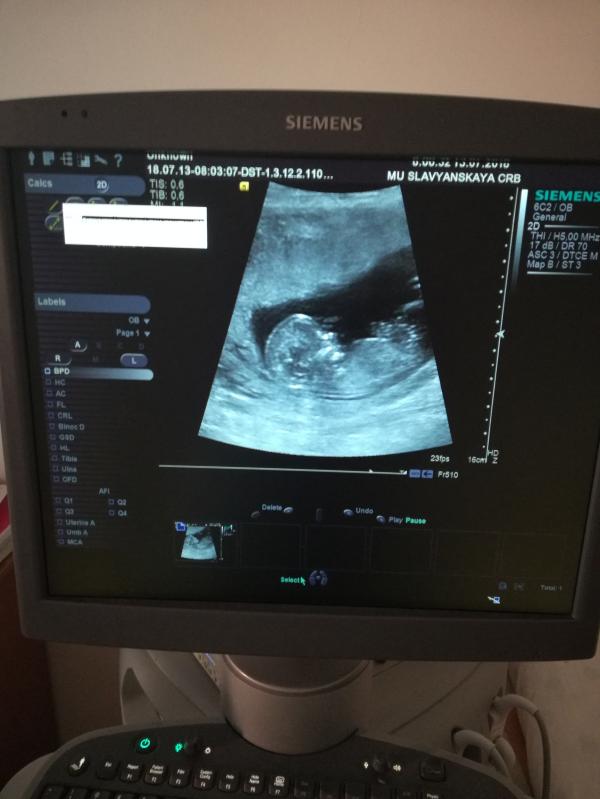

Девчонки, спасибо всем, кто вчера ответил, рассказал про Славянск❤️🙏. Прошло все чудесно, Хачатрян Ш. Г. -шикарная девушка 😍все рассказала, показала, посмеялись, поболтали. Я в восторге!!!! 😍У нас будет ещё мальчишка 👶.

Оооо. Круто! Поздравляю!!! А срок совпал?